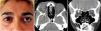

La penetración de un cuerpo extraño en el espacio orbitario intraconal plantea un desafío quirúrgico debido a su ubicación profunda detrás del globo y cercana al nervio óptico. Presentamos un caso de un perdigón alojado en el ápex orbitario en el que se realizó una orbitotomía superolateral a través de un abordaje coronal para su extracción. Esta técnica craneofacial adicional es segura para acceder a la zona lateral intraconal en el caso inusual de necesitar extraer un cuerpo extraño orbitario.

A foreign body penetrating into the intraconal orbital compartment poses a surgical challenge because of its deep location behind the globe and near the optic nerve. We present a case of an air gun pellet lodged into the orbital apex, which was removed via superolateral orbitotomy through coronal incision. This additional craniofacial technique is a safe procedure to access the lateral aspect of the intraconal compartment in the unusual event of having to remove an orbital foreign body.